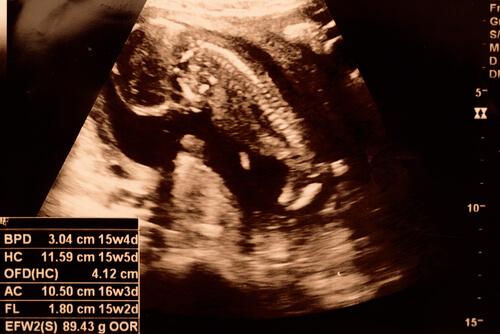

Le bébé lors de la quinzième semaine de grossesse

Il est possible que le bébé laisse apercevoir son sexe lors de l’échographie. En outre, ses bras et ses pieds grandissent. Il lui est désormais possible de bouger les articulations.

Lors de la quinzième semaine de grossesse, le squelette du bébé n’est pas encore complètement formé. Néanmoins, l’on peut voir sa colonne vertébrale avec les terminaisons nerveuses. En outre, il est capable de lever son cou et ses mains. L’on peut parfois voir le bébé mettre ses doigts à la bouche.